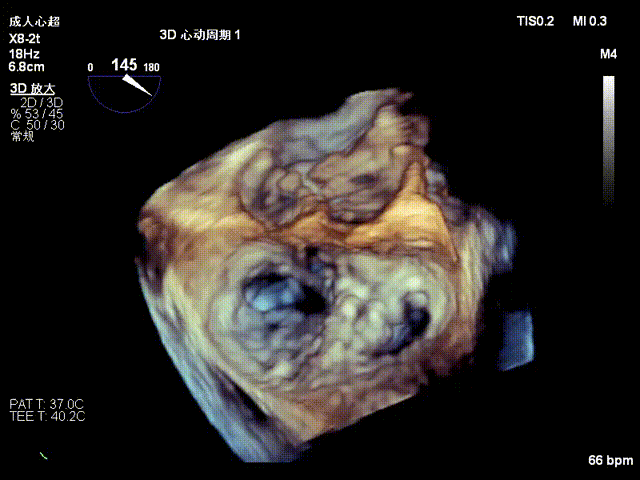

术后二尖瓣反流降至微量,瓣膜夹稳定,功能良好